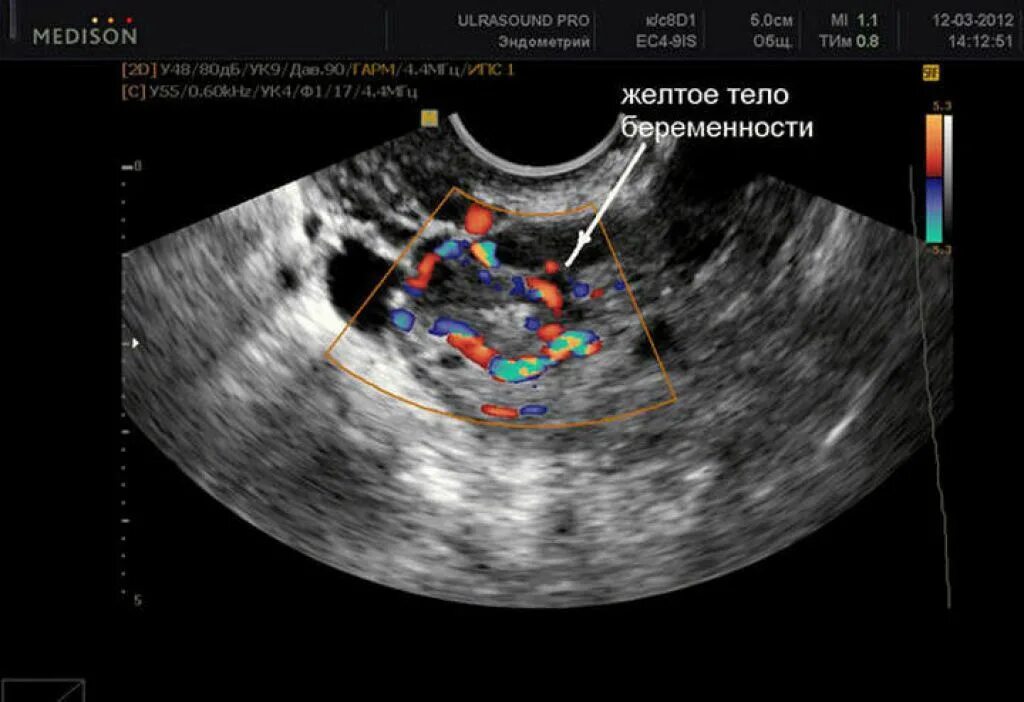

Беременна 2 недели срок